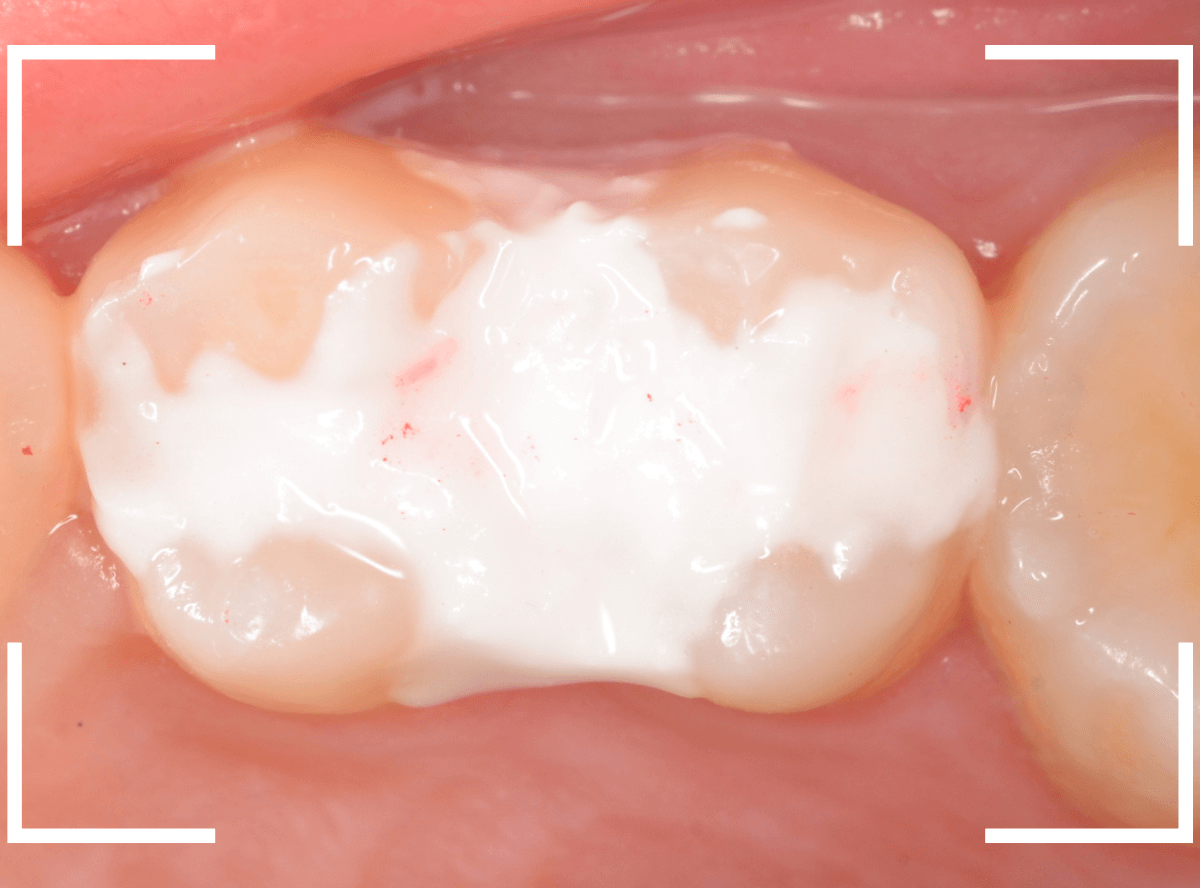

Case.24 レジンの下で虫歯が進行

上の奥歯の虫歯が見つかった患者さんです。

初診のチェックの際に、上から目視すると、レジンがつめてある〇部分が薄暗く黒くなっているので、これは虫歯があるな、とわかりました。

レントゲン写真で確認します。

赤いラインが虫歯と思われる部分、青いラインが歯の神経です。

先ほどの〇部分は明らかな虫歯になっているのがわかります。

この辺りはレジンがつめてありますが、その下もうっすらと虫歯になっていそうです。

治療を開始します。

先ほどの黒く見えた部分は少し削るとすぐに虫歯が出てきました。

手前の歯まで虫歯を除去した時点で、う蝕検知液で確認します。

赤く染色されている部分が虫歯です。

思ったよりも深めの虫歯ですね。

レジンを除去して虫歯をすべて治療したところです。

レジンの中も全体にうっすらと虫歯になっていました。

このくらいの虫歯でも、患者さんは自覚症状はありませんでした。

ご自身の自覚症状だけでは、虫歯の状況がわからないですし、自然に虫歯が治る事もありません。

いつものお話ですが、定期的なメンテナンスで、虫歯の早期発見・治療を心がけましょう。